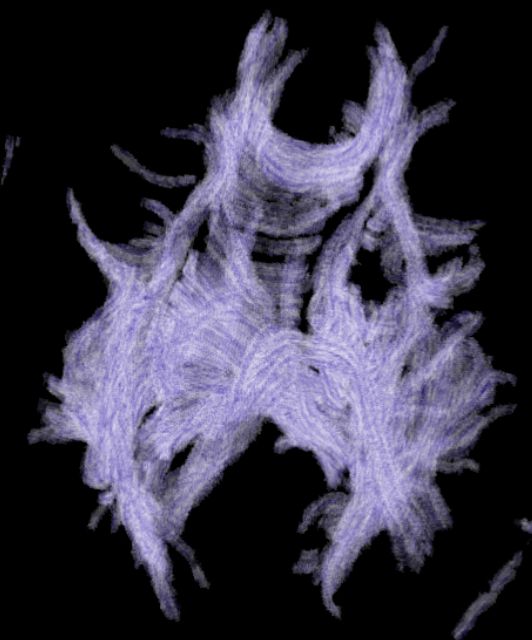

Visualization of the nerve fiber tracts in the brain using a direct volume rendered LIC texture

2004-11-06, Sayuj Harindranath, Desmond Chik, Moqing Zhang, Xin Zhang, Jacky Kwok |

Direct Volume Rendering Fast Line Integral Convolution Image of Human Brain Nerve Fiber Tracts

2004-10-22, Bo Li, Jing Li, Sharon Liu, Jessica Qu, Fung Yang |